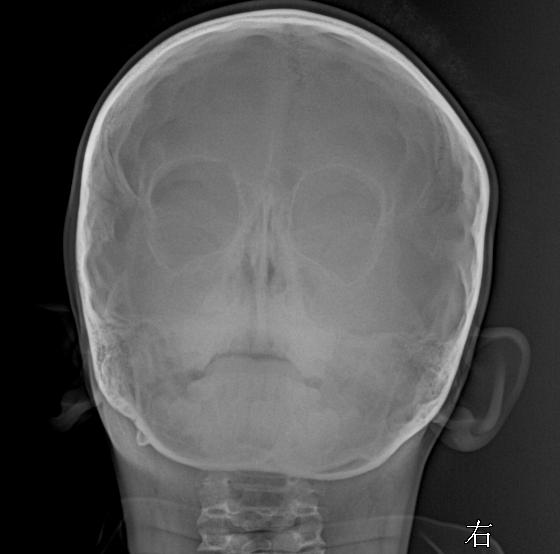

柯瓦氏位,副鼻窦有无问题家人们